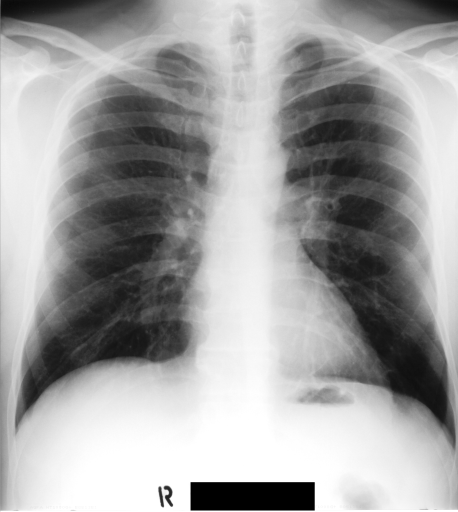

Figure 2 shows barcode annotations for two medical images from IRMA dataset [34, 35] for different values (see lines 4 and 10 in Algorithm 1). Hence, the algorithm works with equidistant angles of projection.

In this section, we report two series of experiments. The first one verifies the correctness or reliability of the micro-DE algorithm to find optimal projections compared to an exhaustive search when we are looking for 4 optimal projection angles out of 16 equidistant angles. In the second experiments, we still provide the results for exhaustive 4/16 selection but examine the evolutionary approach to get 4/180 and 8/180 to investigate the reconstruction accuracy of the micro-DE via correlation of the input image and the reconstructed image using 4/16 (exhaustive), 4/180 (micro-DE) and 8/180 (micro-DE). To conduct the experiments we used 50 images from IRMA dataset [34, 35], a benchmarking collection of 14,400 x-rays images. We selected 10 random classes out of 58 classes, and for each class, we randomly drew 5 images to be used in our experiments. Figure 4 shows the images we have used.

In this series of experiments, we randomly selected three categories from IRMA dataset (namely, breast, foot and lung), and for each category we choose 5 random images from that class (Figures 5, 6 and 7 show these images). When we find “4 out of 180” (4/180) and “8 out of 180” (8/180) projections via micro-DE (tasks that cannot be performed via brute-force), then the question is what can we say about the reconstruction error, in terms of correlation between original and reconstructed images, when we compare evolutionary approximation with the case that we can manage via exhaustive search, namely “4 out of 16” (4/16)? Can micro-DE reach at least the same correlation (similarity) as the brute-force case in lower dimensions? If yes, we may have more confidence in using micro-DE in practice where we cannot apply brute force for benchmarking or direct use, especially for higher dimensions (i.e., the number of projections).